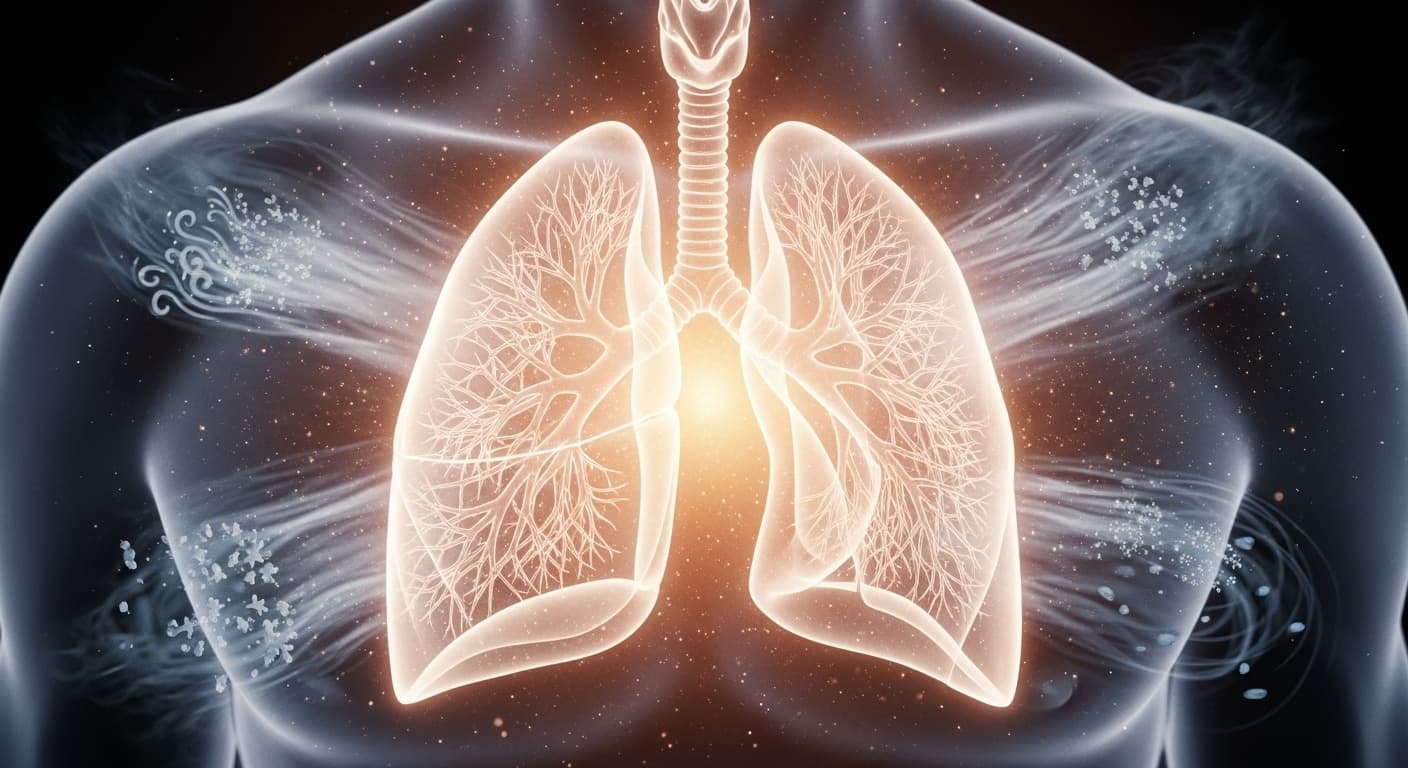

鼻者肺之竅也。肺氣和則鼻和,肺氣不和則鼻病也。

코는 폐의 구멍이다. 폐기가 조화로우면 코가 조화롭고, 폐기가 조화롭지 못하면 코에 병이 생긴다.